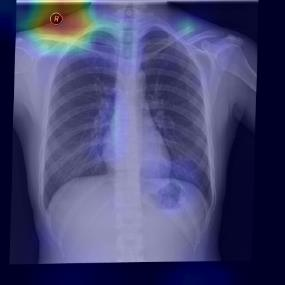

Chest X-ray (CXR) is the most typical diagnostic X-ray examination for screening various thoracic diseases. Automatically localizing lesions from CXR is promising for alleviating radiologists' reading burden. However, CXR datasets are often with massive image-level annotations and scarce lesion-level annotations, and more often, without annotations. Thus far, unifying different supervision granularities to develop thoracic disease detection algorithms has not been comprehensively addressed. In this paper, we present OXnet, the first deep omni-supervised thoracic disease detection network to our best knowledge that uses as much available supervision as possible for CXR diagnosis. We first introduce supervised learning via a one-stage detection model. Then, we inject a global classification head to the detection model and propose dual attention alignment to guide the global gradient to the local detection branch, which enables learning lesion detection from image-level annotations. We also impose intra-class compactness and inter-class separability with global prototype alignment to further enhance the global information learning. Moreover, we leverage a soft focal loss to distill the soft pseudo-labels of unlabeled data generated by a teacher model. Extensive experiments on a large-scale chest X-ray dataset show the proposed OXnet outperforms competitive methods with significant margins. Further, we investigate omni-supervision under various annotation granularities and corroborate OXnet is a promising choice to mitigate the plight of annotation shortage for medical image diagnosis.